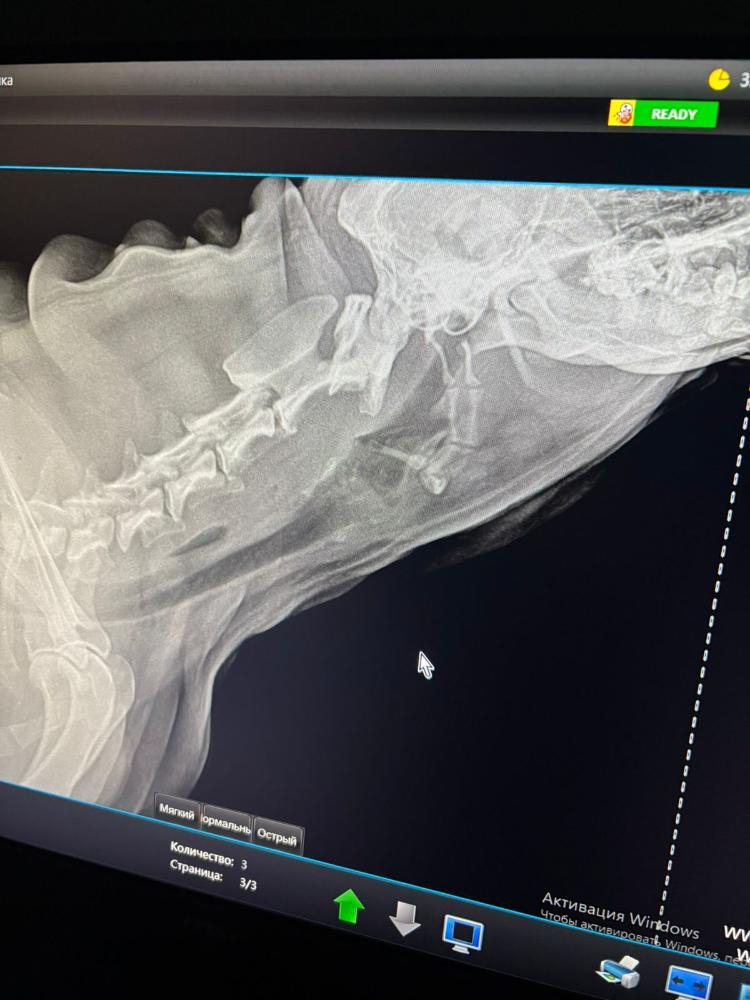

Первое что подумали конечно МТС в лёгких. Но по снимку их пока не видят.

По снимку что то не понятное в пищеводе.

В четверг есть шанс попасть на эндоскопию. В 9 утра. Нам нужно понять причину кашля. Кашель не лёгочный. А вот именно странный пищеводный.